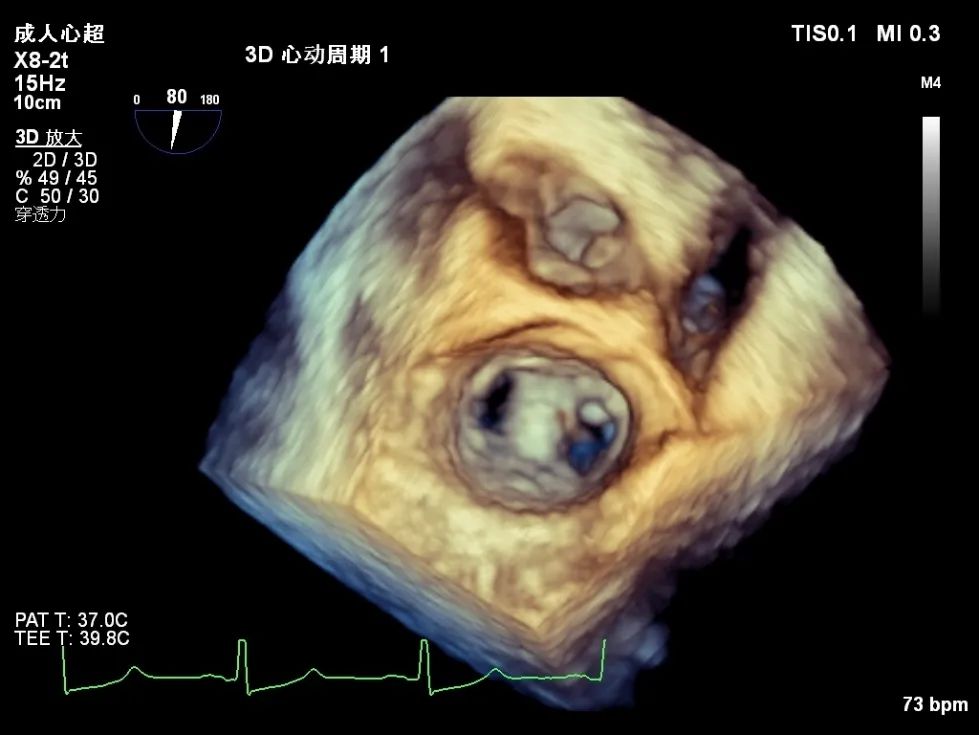

术前超声心动图

心脏超声检查提示:二尖瓣后叶(P2)脱垂,并存在腱索断裂,重度二尖瓣反流。